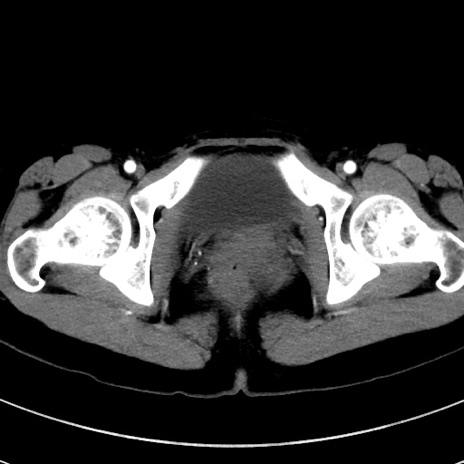

症例17(横断像)

【症例】20歳代女性

【主訴】嘔吐、下腹部痛

【現病歴】昨日夕食後に嘔吐し下腹部痛が出現。本日になっても嘔吐持続し改善しないため来院。

【身体所見】意識清明、BT 37.2℃、BP 108/67mmHg、腹部:平坦、やや硬、下腹部正中から右にかけて圧痛あり、反跳痛軽度あり、tapping pain(+)。

【データ】WBC 13600、CRP 14.94

冠状断像